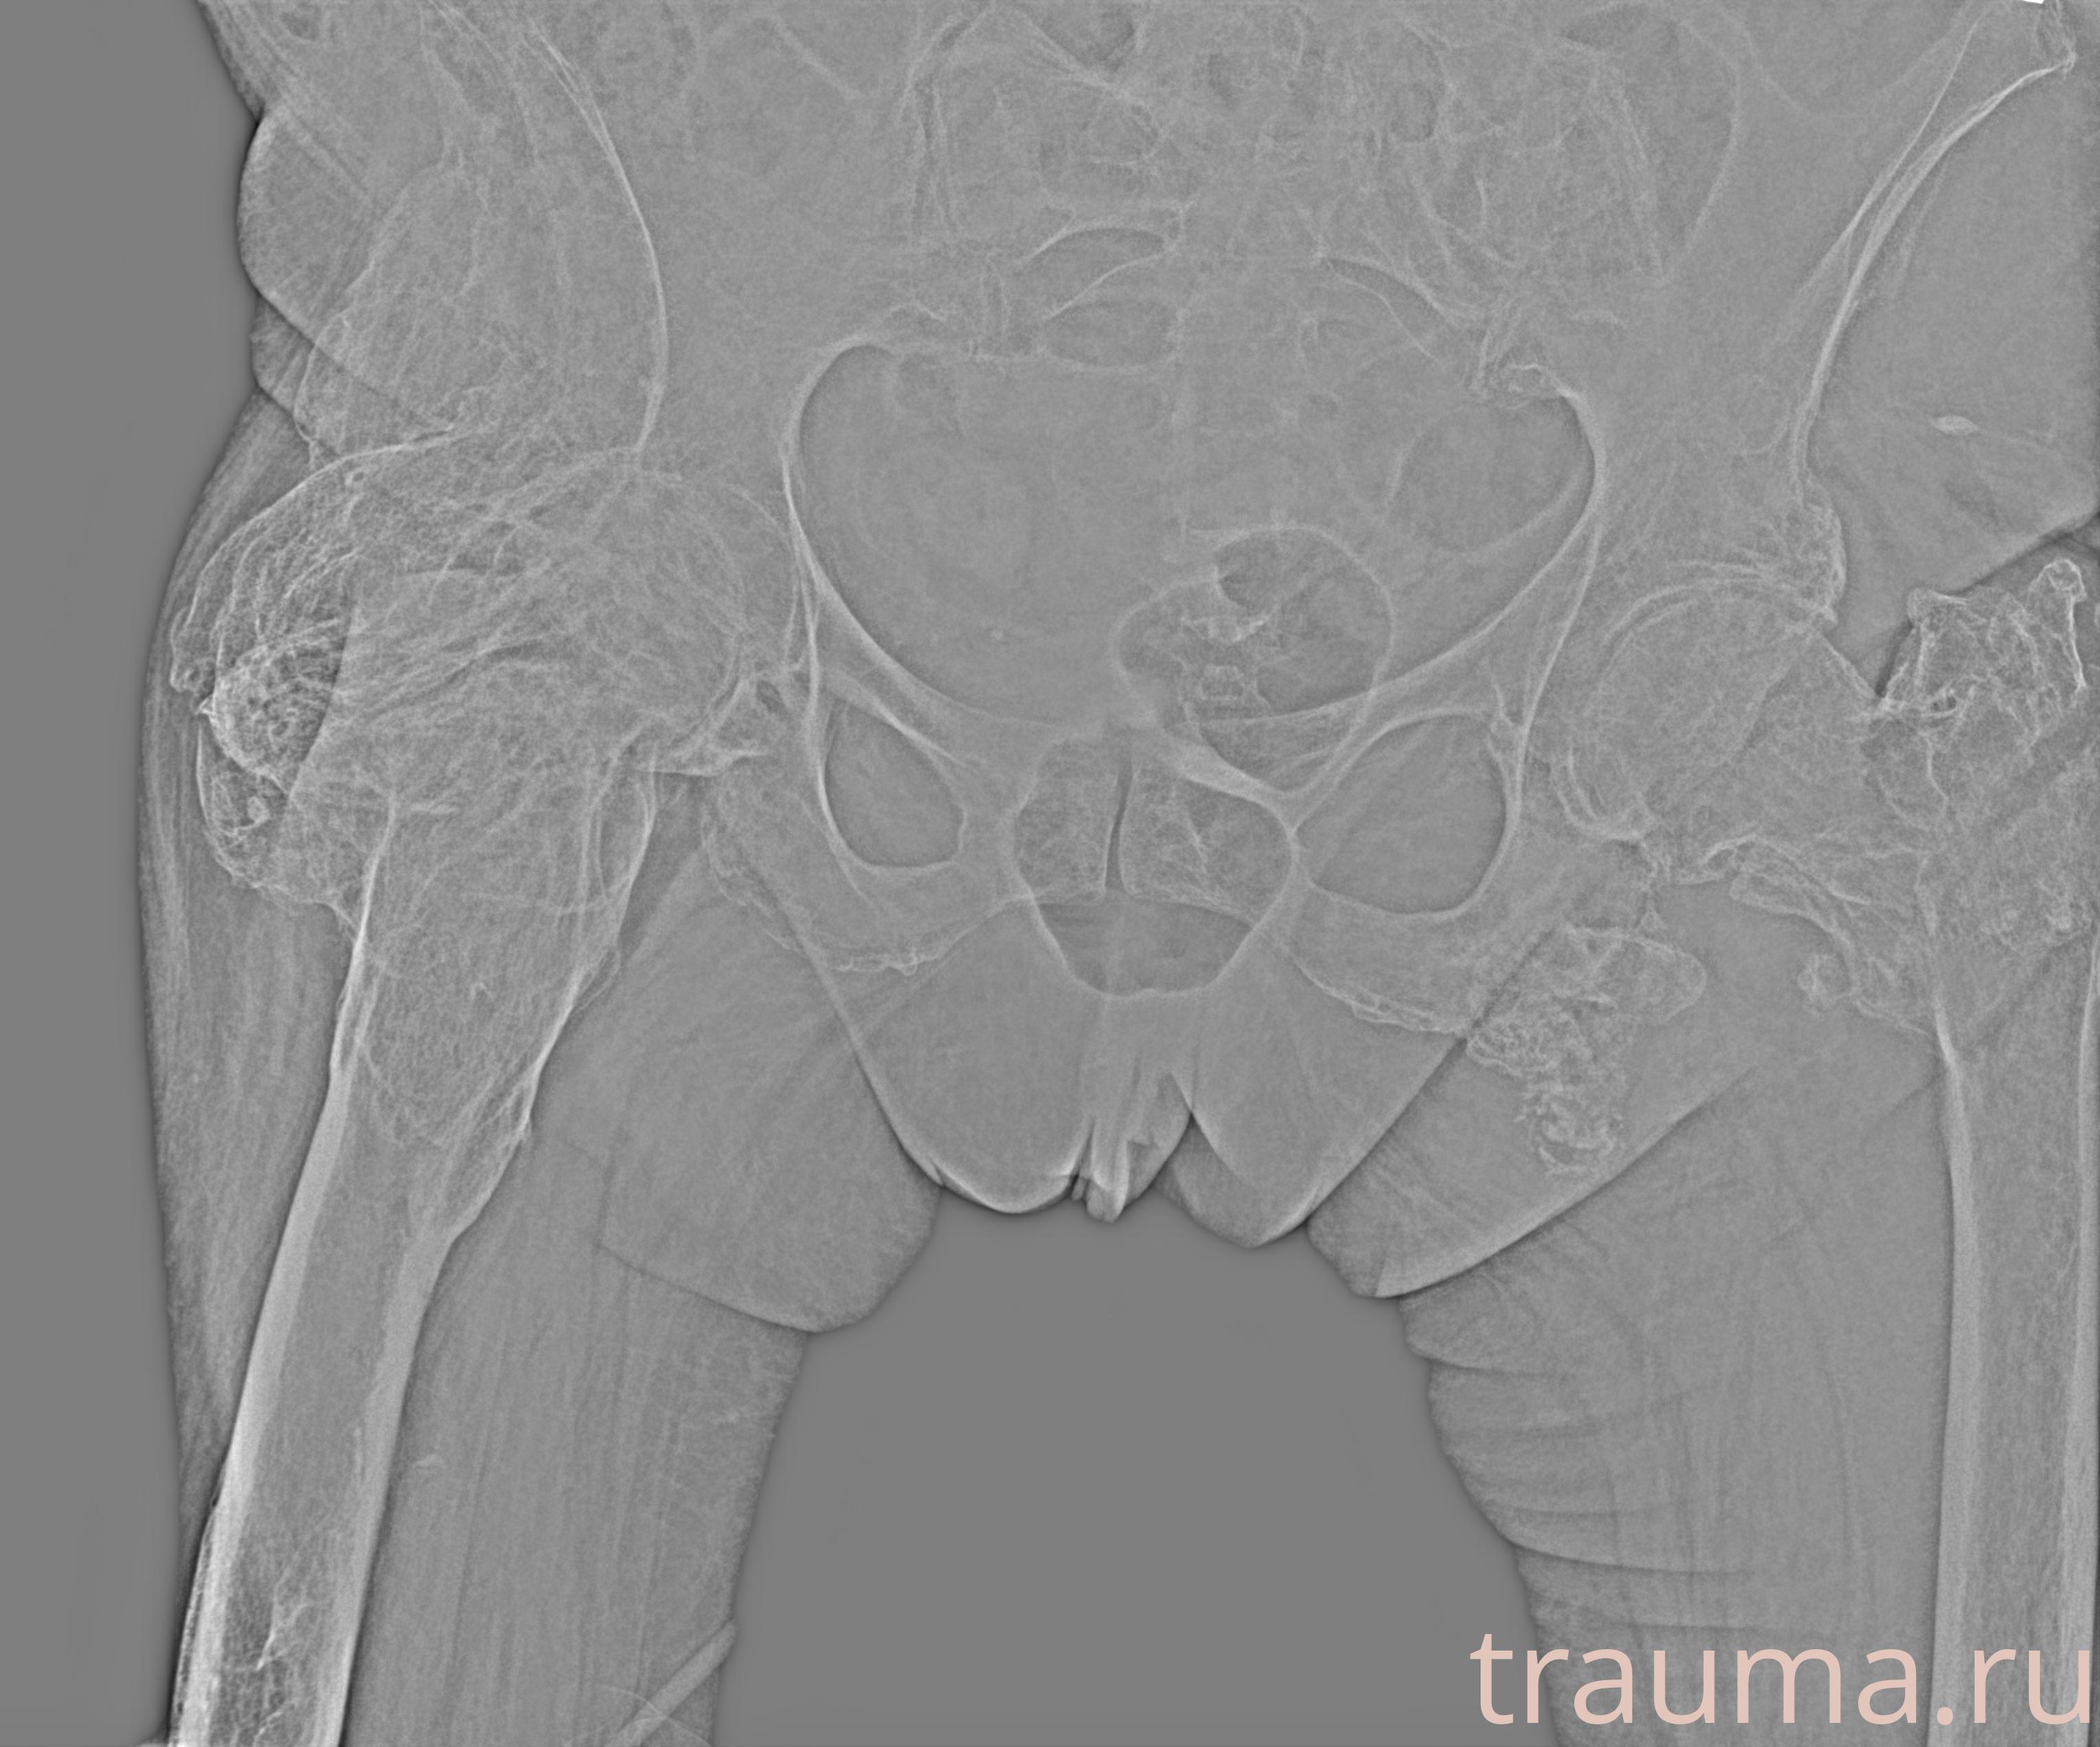

Рентген на дому: по вашему адресу приезжает врач-рентгенолог, травматолог-ортопед с мобильным рентгеновским аппаратом, проводит диагностику травмы или заболевания, делает необходимые рентгенограммы, дает рекомендации по дальнейшему лечению. Получить качественные снимки в домашних условиях возможно благодаря уникальной методике, разработанной МосРентген Центром для института  Склифосовского